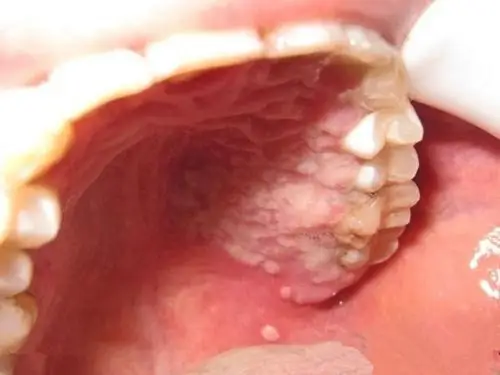

口腔白斑病